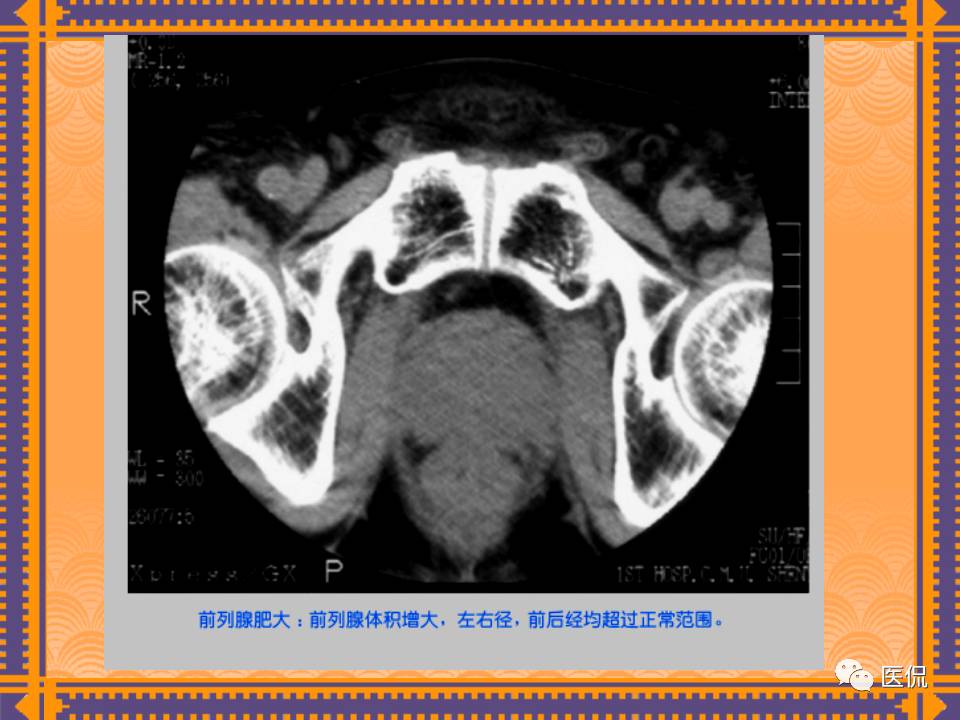

这篇PPT对男性生殖系统疾病:前列腺增生、前列腺癌;女性生殖系统疾病:子宫肌瘤、子宫癌、卵巢囊肿和卵巢肿瘤以及腹膜后间隙疾病进行了详细讲解。